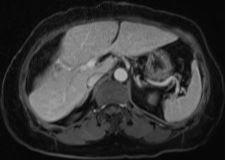

結腸腫瘤是指發(fā)生在結腸部位的腫瘤,可分為良性和惡性,結腸腫瘤早期癥狀不明顯,隨著病情發(fā)展,可能出現腹痛、便血、腸梗阻等癥狀,治療方法包括手術、化療、放療等,具體治療方案需根據患者的具體情況制定。